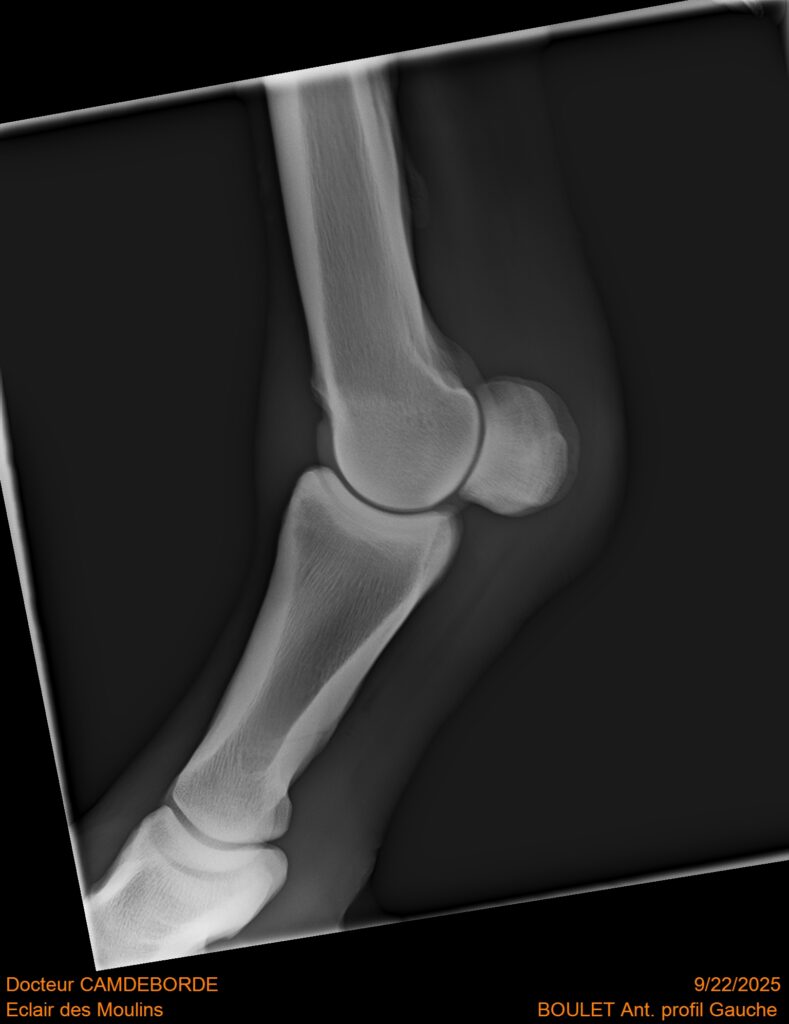

10 K ✨ TOP cheval pour épreuve Amateur ! ECLAIR DES MOULINS, selle Français de 11 ans. Classé sur 1m05. Idéal pour aller faire jusqu’à 110 voir 115, cheval pas usé (une vingtaines de parcours). Très gentil au quotidien, cheval de famille. Courageux et respectueux à l’obstacle. Bien dressé, change de pieds. Bilan pieds, boulets, jarrets, grassets et visite clinique effectuée cette semaine. il peut vivre au box comme au champs, cheval rustique. toise environ 1m60 porteur. Pour le compte de son propriétaire car manque de temps.

RADIOS ET CLINIQUE